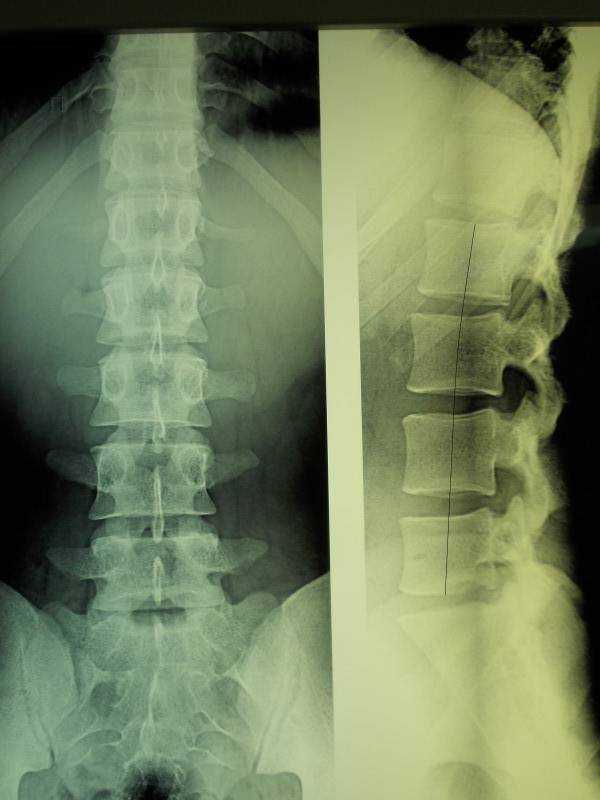

Медицинские снимки: рентген позвоночника сбоку